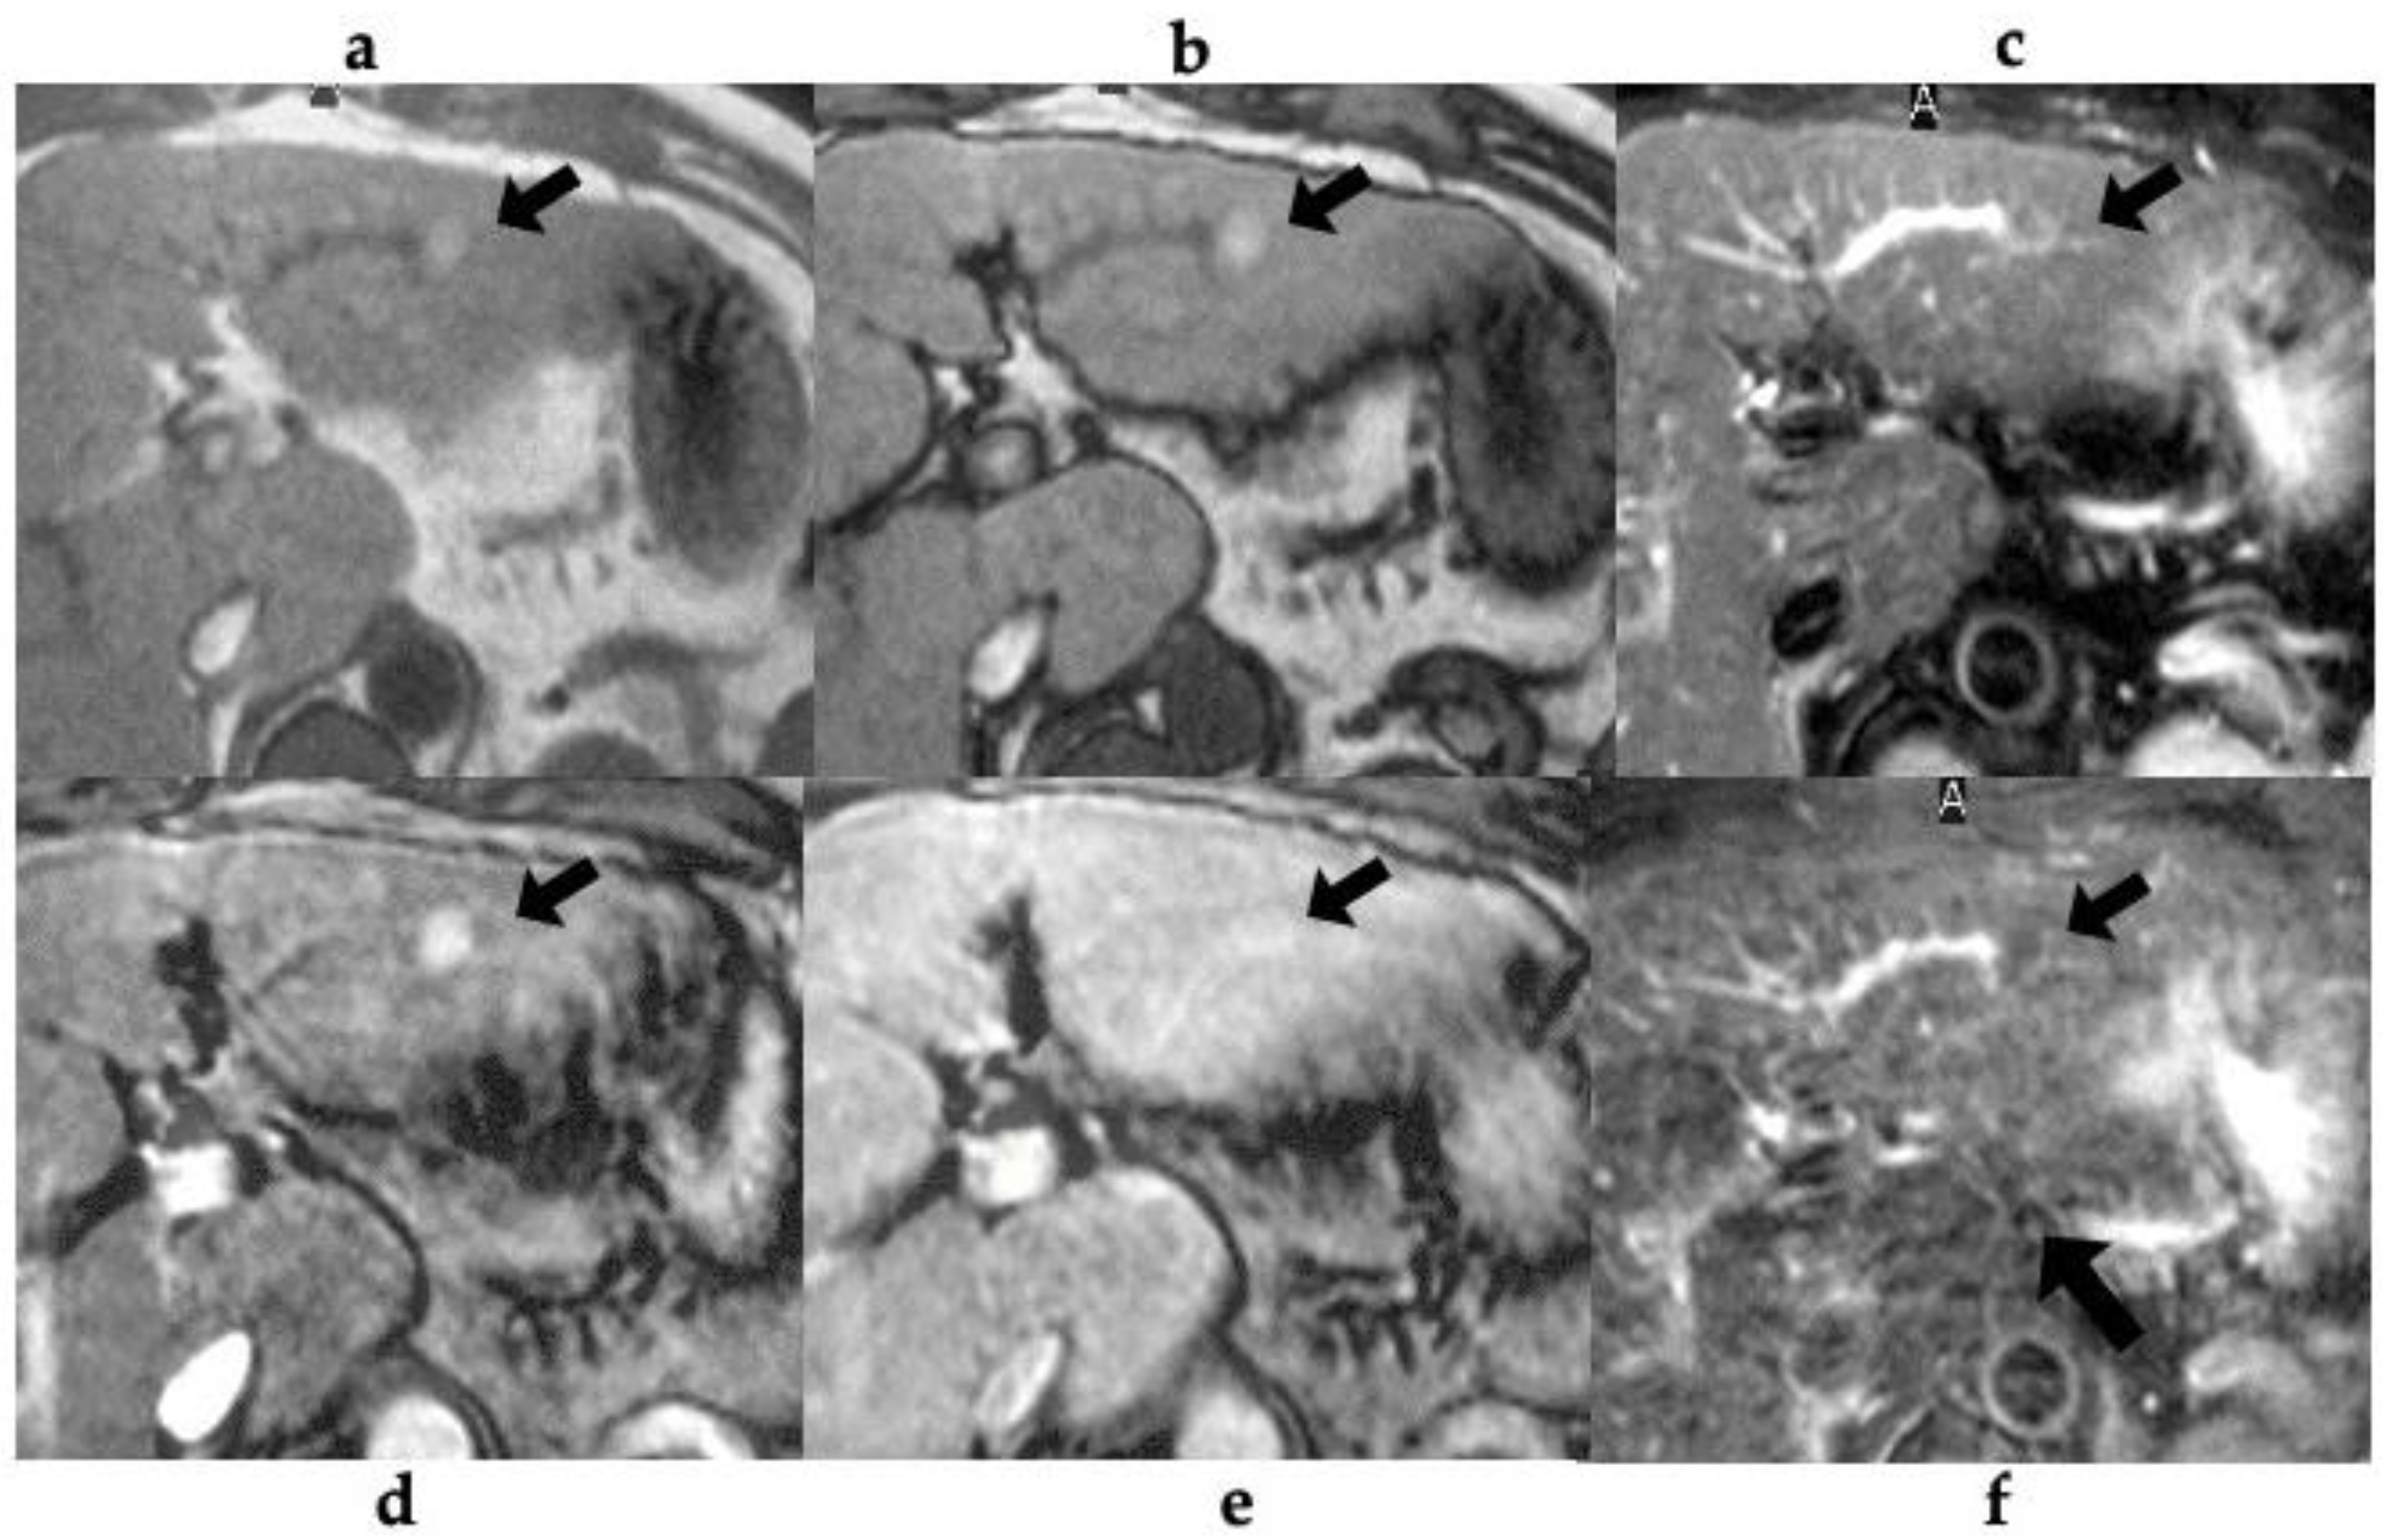

Figure 1. 58-year-old man with alcoholic liver cirrhosis (patient no. 5). (a-b) T1-weighted gradient-echo (GRE) MR (a; in-phase, b; opposed-phase) image shows a small and high-signal-intensity nodule (arrow) in the lateral segment. (c) T2-weighted fast spin-echo MR image shows iso intensity nodule (arrow). Gadolinium-enhanced T1-weighted GRE MR imaging obtained during the (d) arterial- and (e) portal-venous phase reveals a nodule with arterial phase hyperenhancement (arrow) and without washout (arrow). (f) The SPIO-enhanced T2*-weighted GRE MR image shows the lesion as a low-signal intensity nodule (arrow) with SPIO-uptake compared with the surrounding liver parenchyma.

Table 3 shows the MRI findings of the FNH-like lesions. Among the thirteen patients with FNH-like lesions, eleven (85%) showed high or iso-high intensity on T1WI, seven (54%) showed iso-high intensity on T2WI, six (46%) showed low intensity, three (23%) showed high-intensity central scars, and 10 (77%) showed no central scars on T2WI. Chemical shift artefacts were observed in all the 13 patients with FNH-like lesions (Figure 1 and Figure 2). In the six patients who underwent gadoxetic acid-enhanced MRI (Figure 3 and Figure 4), all lesions exhibited marked homogeneous enhancement during the arterial phase. Two enhancement patterns were observed on the HBP: heterogeneous hyperintense (n = 3, 43%) and ring-like enhancement (n = 4, 57%). In the eight patients who underwent SPIO-enhanced MRI, all lesions exhibited a marked homogeneous uptake pattern on post-SPIO-enhanced MRI (Figure 1 and Figure 3).